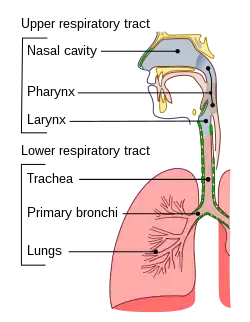

En luftvejsinfektion er en infektionssygdom, der involverer luftvejene. Denne type infektioner inddeles normalt i øvre luftvejsinfektioner og nedre luftvejsinfektioner. Nedre luftvejsinfektioner, såsom lungebetændelse, er oftest langt mere alvorlige end øvre luftvejsinfektioner, såsom forkølelse.

Selvom der hersker nogen uenighed om den præcise grænse mellem de øvre og nedre luftveje, betragtes de øvre luftveje almindeligvis som hulrummet over stemmebåndene. Dette inkluderer næsen, bihulerne, svælget og strubehovedet.

De nedre luftveje består af luftrøret, bronkierne, bronkiolerne og lungerne.